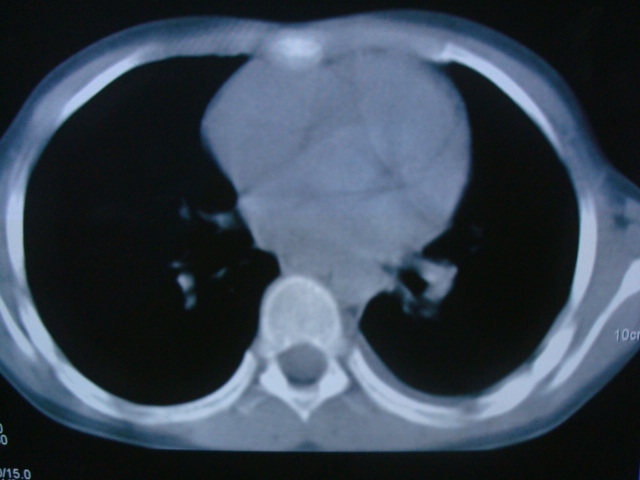

标题: PED0869:男,10岁,肺内多发结节+胸水 [打印本页]

标题: PED0869:男,10岁,肺内多发结节+胸水

男,10岁,左胸痛,发热轻,血象高。后到省级权威医院治疗,病情明显好转,结果几天后公布。老机器,图像质量差,见谅。